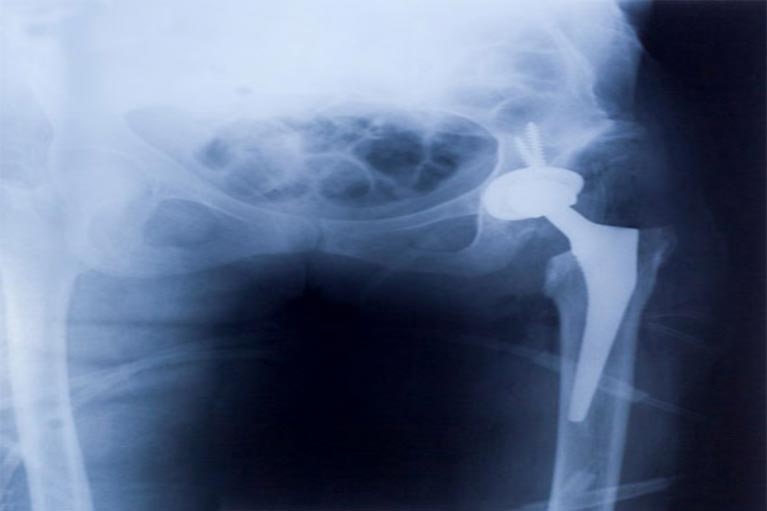

- Defective Medical Devices – Hip / Joint Replacement, Heart Valves, Zeiss Opthalmic System, Bypass Connectors, Patient Lifts